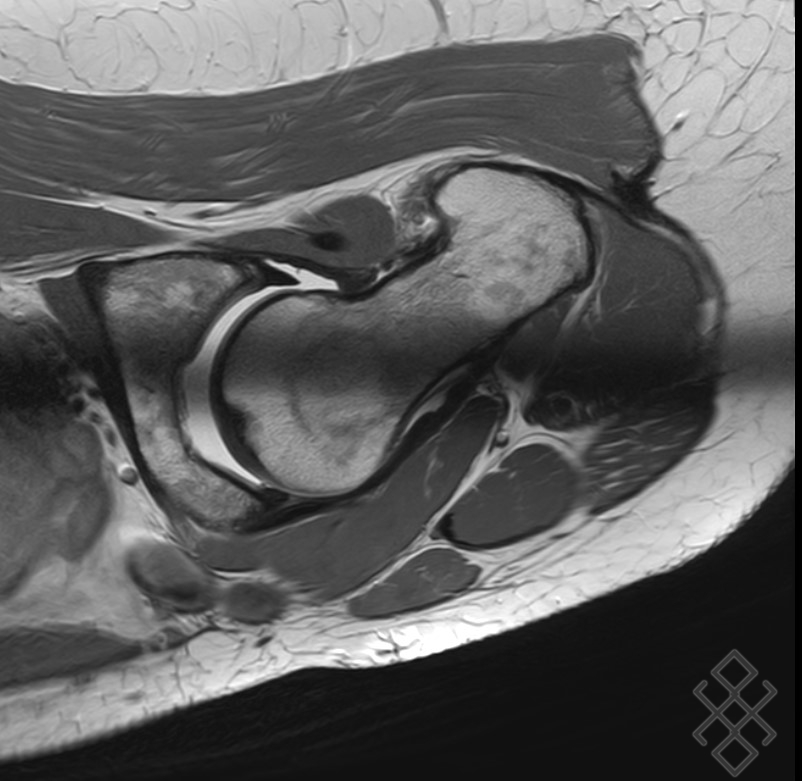

IRM du bassin, coupe horizontale, séquence STIR. Une IRM pelvienne crée des images de la zone située entre les deux hanches Il permet en particulier de rechercher : une inflammation des tendons (tendinite) des muscles gluteaux (fessiers) Une arthropathie de hanche (atteinte de l'articulation entre le fémur et le bassin) un épanchement dans l'articulation coxo.

IRM du bassin et des hanches Imagerie Médicale du Mâconnais. Elle a pour intérêt une approche optimale de la ceinture pelvienne aussi bien pour ses composants ostéo-cartilagineux que pour les tissus mous adjacents. Deux types de population sont touchées par les douleurs de hanches : - Les sportifs (arts martiaux, danse…) peuvent à force de mouvement amples provoquer une usure trop rapide d'un petit coussinet dans l'articulation entre le bassin et la hanche (le labrum de l'articulation coxo-fémorale) ce qui peut provoquer des douleurs chroniques notamment, le bilan de sa lésion est par.